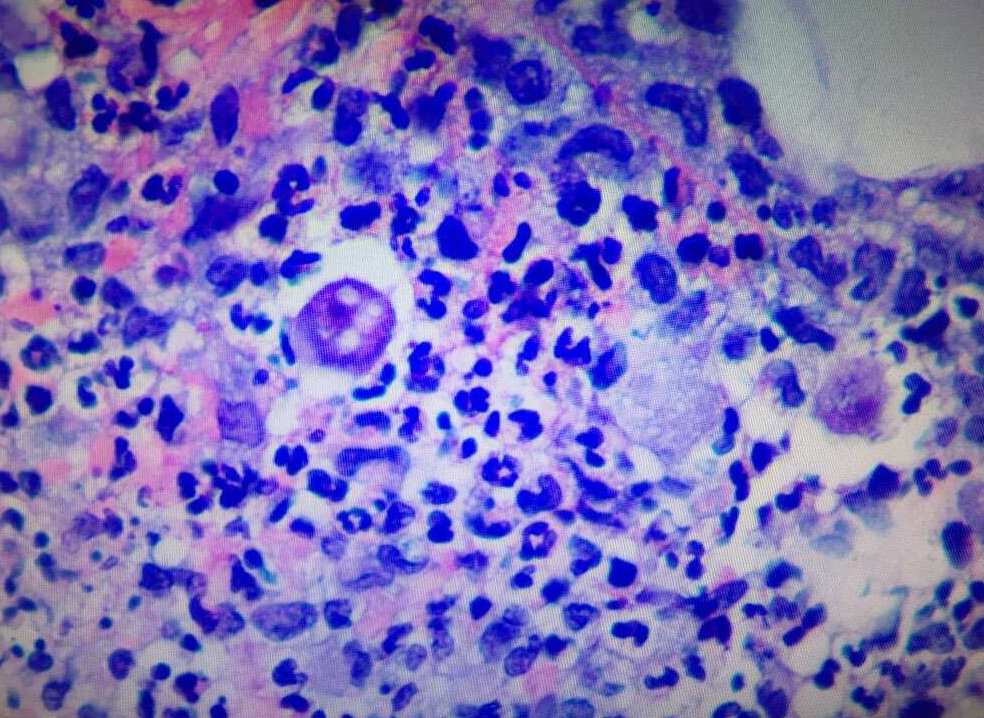

The second biopsy of the lesion was sent for hematoxylin and eosin (H&E) staining and tissue cultures, including atypical mycobacteria and opportunistic fungi (Figures 2 and 3).

Figure 3. H&E staining of same biopsy at ×20 magnification. Note the trophozoite with a agenta-colored nucleus and prominent nucleoli at center of image.